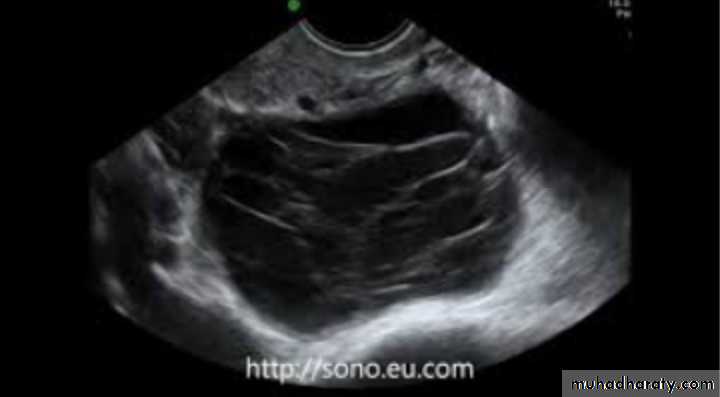

Dx: multilocular ovarian cyst

Risk: malignancyPCOS